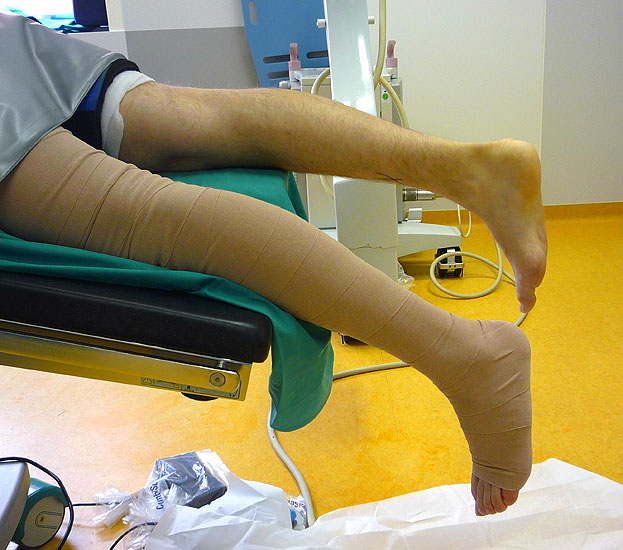

• Bauchlagerung, das distale Drittel des Unterschenkels hängt über die Tischkante hinaus, das kontralaterale Bein wird abgesenkt. Es sollte darauf geachtet werden, dass der Fuß streng orthograd ausgerichtet ist (Abbildung Nr. 1 und 2).